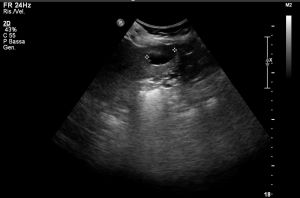

Ad oggi sono state identificate con l’ecografia addominale prevista dal protocollo, 9 neoplasie del parenchima epatico: 5 angiosarcomi (Fig. 1-4) (di cui 2 viventi) e 4 epatocarcinomi (Fig. 5-7) (di cui 1 vivente), successivamente sottoposte a studio TC e tutte confermate dalla diagnosi istologica.

Fig.1. Caso 1 di angiosarcoma epatico

Fig.2. Caso 1 di angiosarcoma epatico